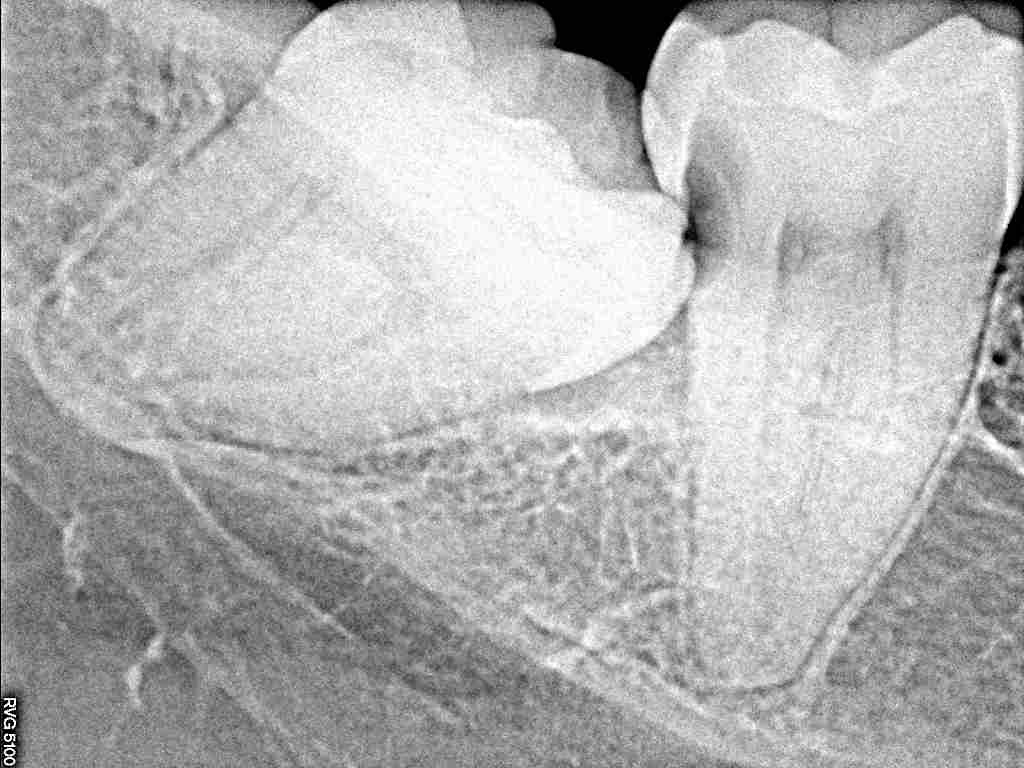

デンタルレントゲンでも歯が大きいのがわかります

一つ手前の歯にも重篤にもなりかねない虫歯を作っています